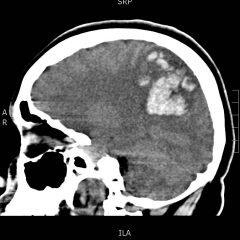

Intracranial Hemorrhage Following a 3-week...

23 Jan, 17